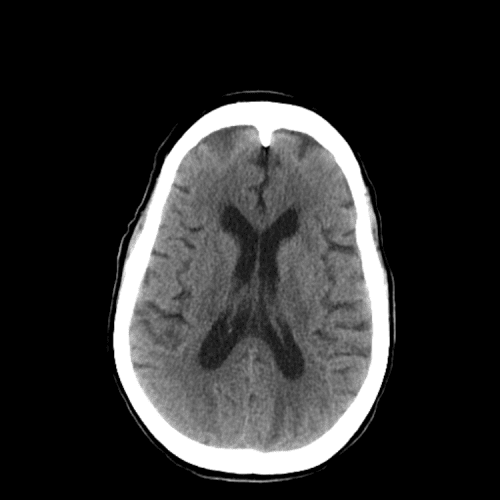

cerebral edema